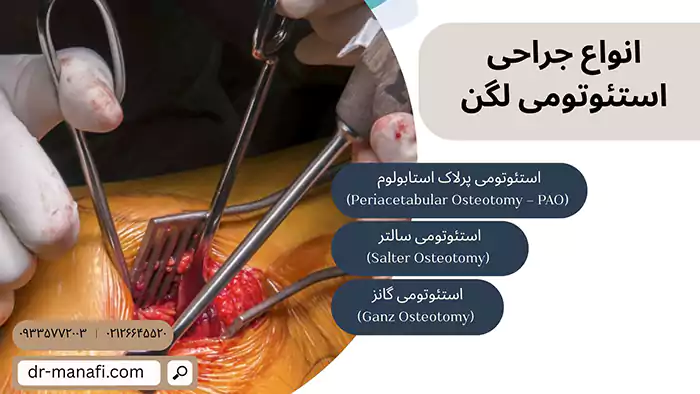

انواع جراحی استئوتومی لگن

روشهای مختلفی برای استئوتومی لگن وجود دارد که در ادامه هریک را بررسی میکنیم:

استئوتومی پرلاک استابولوم (Periacetabular Osteotomy – PAO)

رایجترین روش در بزرگسالان و جوانان است. در این تکنیک، اطراف حفره لگن (استابولوم) در چند نقطه برش داده میشود و سپس کل حفره در زاویهای جدید قرار میگیرد تا پوشش بهتری روی سر استخوان ران ایجاد شود. این روش کمک میکند فشار از روی مفصل برداشته شده و خطر آرتروز کاهش یابد.

استئوتومی سالتر (Salter Osteotomy)

بیشتر در کودکان و نوجوانان استفاده میشود. در این روش، استخوان لگن در قسمت ایلیوم (بالای لگن) یک برش ایجاد میشود و با استفاده از پیوند استخوانی یا گرافت، زاویه لگن تغییر داده میشود. این عمل سادهتر از PAO است و معمولاً در سنین پایین نتایج بسیار خوبی دارد.

استئوتومی گانز (Ganz Osteotomy)

این روش شباهت زیادی به PAO دارد اما تکنیک آن کمی متفاوت است. در استئوتومی گانز نیز بخش استابولوم به طور کامل برش داده میشود و قابلیت جابجایی سهبعدی پیدا میکند. این تکنیک بیشتر در بیماران جوان با دیسپلازی متوسط تا شدید استفاده میشود و نیازمند جراح بسیار باتجربه است.